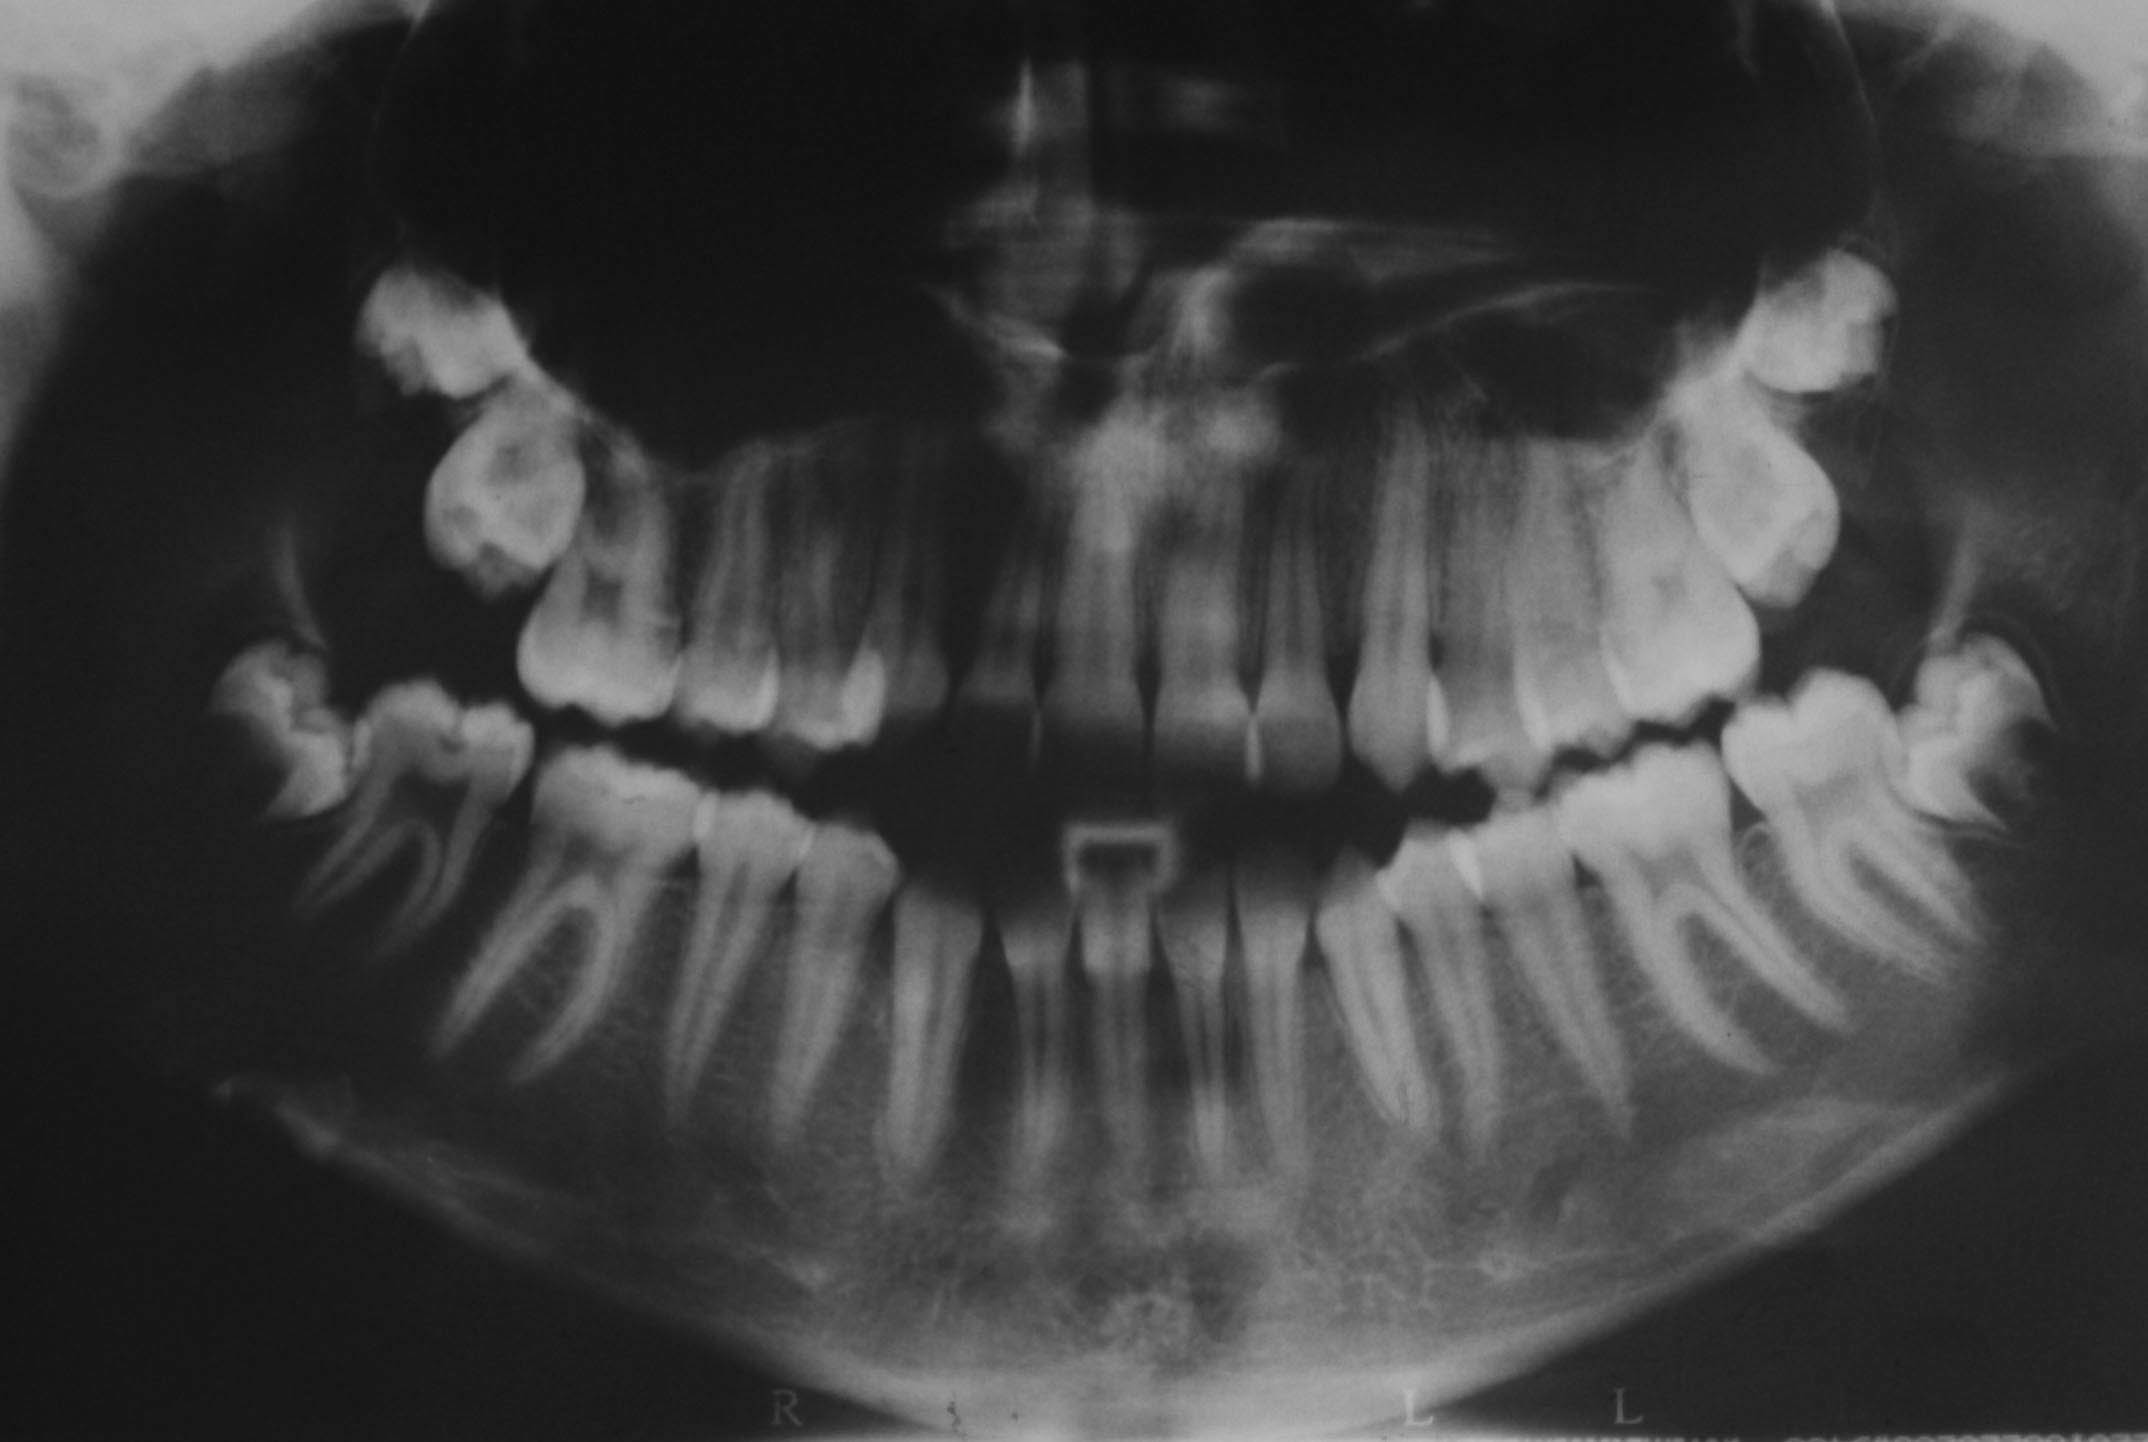

وقتی قرار است که خلفیها بیشتر جلو بیایند، مثلاً در بیمارانی که میل به اپن بایت دارند و کمبود فضا در ناحیه خلفی مشاهده میشود. در این زمان اقدام به کشیدن پرمولر دوم میکنیم. روی هم سوار شدن مولرها در OPG که اصطلاحاً به آن Stacking میگویند (شکل 19-3) نشان از کرادینگ خلفی است. چه این حالت باشد چه میل به اپن بایت داشته باشد، ترجیحاً پرمولر دوم کشیده میشود. بعد از کشیدن پرمولر دوم و تا انتهای درمان مولرها حرکت مزیالی زیادی میکنند. چون در بٌعد باکولینگوالی ریشه پهنی دارند، لذا تنگی آلوئولار پراسس مانع این حرکت میشود. اگر پرمولر دوم را میکشید با تکنیکهای socket preservation ساکت آن را حفظ کنید. عمده بسته شدن فضا در مرحله آخر درمان روی سیم استیل و با فنر آیلتدار انجام میشود. به همین دلیل کشیدن پرمولر دوم را به آن زمان موکول کنید تا تحلیل آلوئولار پراسس که یک فرایند فیزیولوژیک بعد از کشیدن دندان است حداقل باشد.

شکل 19-3: